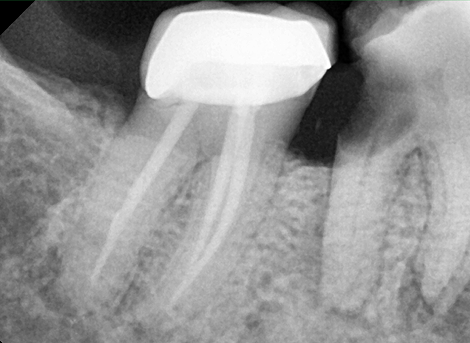

Complete disinfection of the root canal.

Sealing the Canal